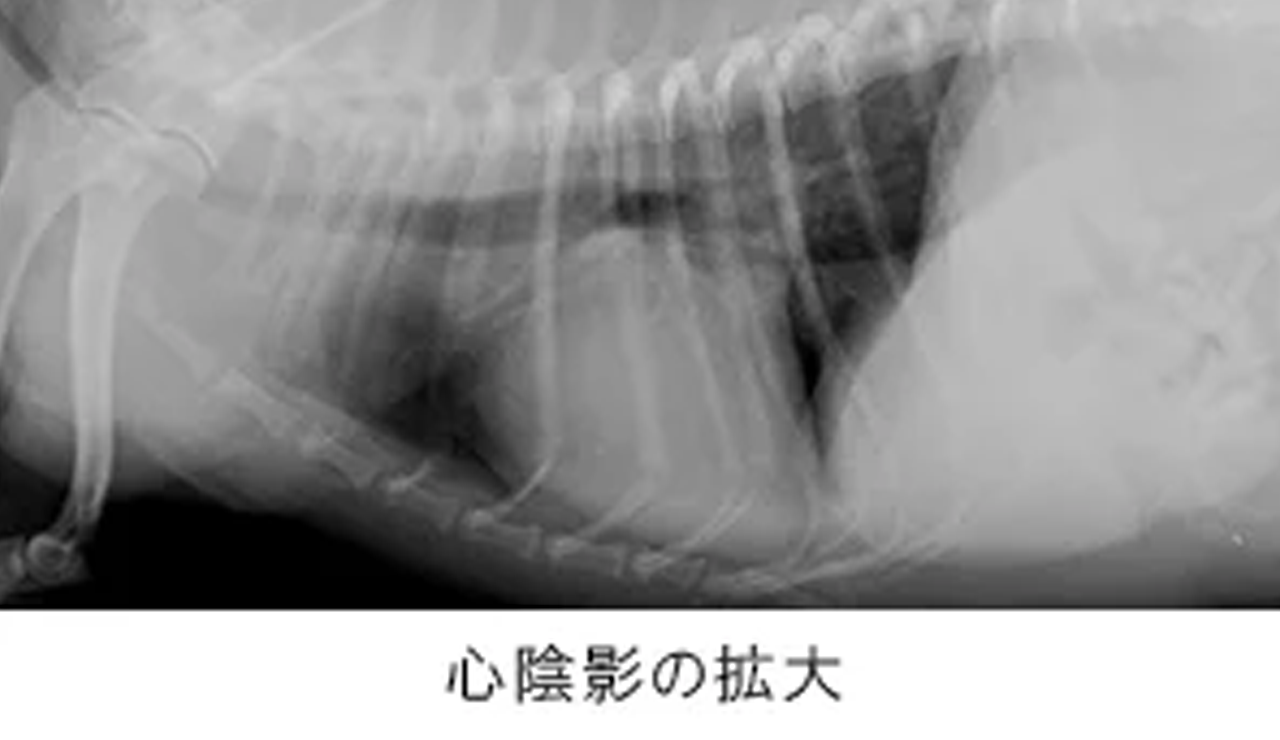

初期には症状が出ないことも多く、精密検査ではじめて発見に至ることも多い動物の心臓病。年齢とともに罹患率も高まり、重篤化しやすいため、定期的な診察を通じて早期発見・早期治療を心がけましょう。

ピジョン動物愛護病院では、各院いずれもレントゲン検査や最新の超音波検査装置による心臓の精密検査を実施しています。

| 痛みを伴うことなく心臓の大きさ・形態や肺の評価を可能にする装置。とくに心不全時に認められる肺水腫の診断に威力を発揮します。 なお、院内には専用のネットワークで機器や各端末が連携しているため、診察室にいながら撮影結果を確認でき、飼い主様への的確なご説明が可能です。 |